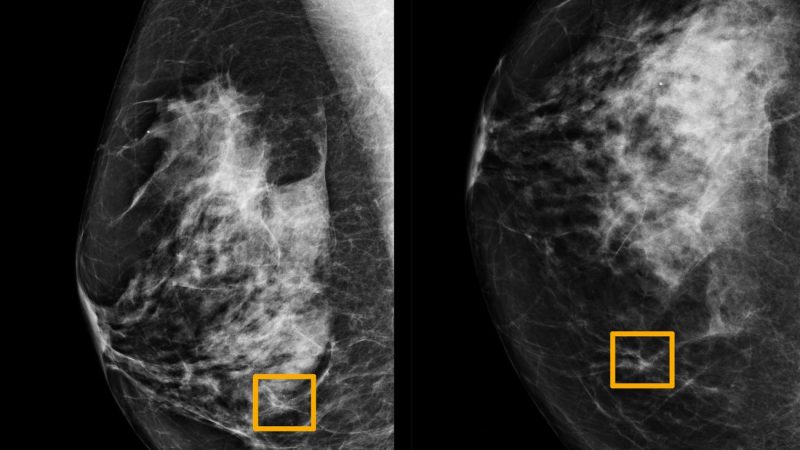

Σύστημα ΑΙ της Google εντοπίζει με ακρίβεια τον καρκίνο του μαστού